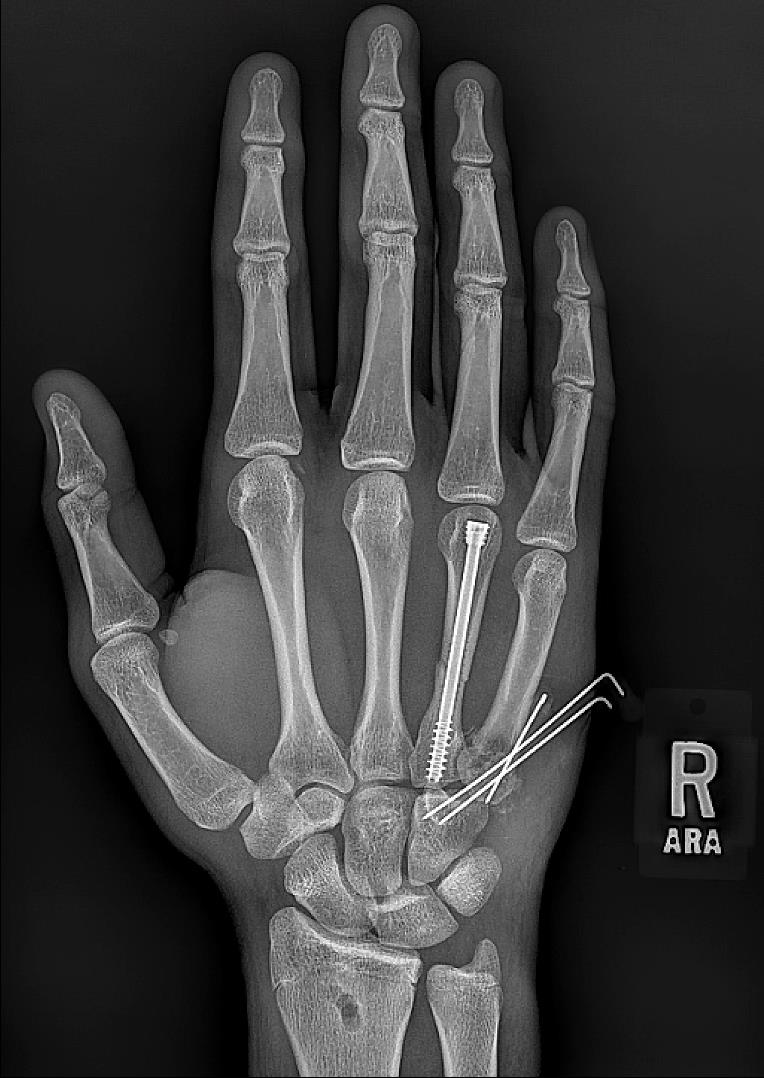

An 18-year-old male presents to your clinic with two weeks of right-hand pain. He reports punching the wall in the locker room after losing in the state championship. Radiographs from today’s visit are shown in Figures A-C. What is the most appropriate treatment at this time?

The radiographs show a displaced, angulated ring finger fracture with a comminuted, intraarticular fracture of the fifth metacarpal base. Given these fracture patterns and the time from injury, operative fixation of both injuries is the most appropriate treatment (Answer 1).

Figures A-C demonstrate a fourth metacarpal shaft fracture with angulation > 30 degrees. The fifth metacarpal base fracture is comminuted and intraarticular with carpometacarpal joint subluxation. Illustration A shows post-operative images of percutaneous pinning of the fifth metacarpal base fracture and intramedullary headless compress screw fixation of the fourth metacarpal. Illustration B shows 12-week post-operative imaging demonstrating union of both fractures.